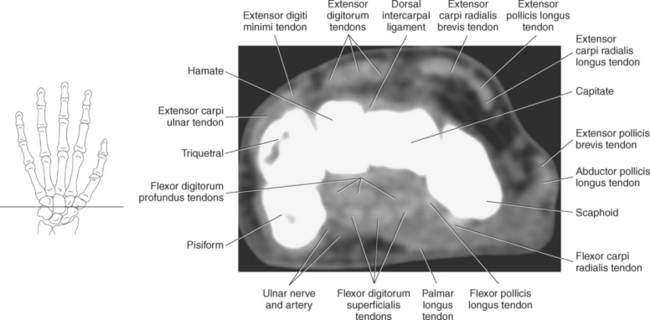

Numerous ligaments provide additional stability to the wrist. The extrinsic ligaments reinforce the joint cavity surrounding the carpal region and include palmar and dorsal radial carpal ligaments, the radial and ulnar collateral ligaments, and the TFCC (Figures 9.115 through 9.117). The many articulations between the carpal bones are supported by the intercarpal ligaments or intrinsic ligaments that connect the carpal bones to each other (Figure 9.115). The configuration of the intrinsic ligaments, metacarpal ligaments, and triangular fibrocartilage complex creates five different joint compartments that can be demonstrated at arthrography: (1) compartment of the first carpometacarpal articulation, (2) common carpometacarpal compartment, (3) mediocarpal compartment, (4) intermetacarpal compartment, and (5) radiocarpal compartment (Figure 9.115). The carpal tunnel is created by the concave arrangement of the carpal bones (Figure 9.103). A thick ligamentous band called the flexor retinaculum (transverse carpal ligament) stretches across the carpal tunnel to create an enclosure for the passage of tendons and the median nerve (Figures 9.118 through 9.120). The flexor retinaculum inserts medially on the pisiform and hook of the hamate and spans the wrist to insert laterally on the scaphoid and trapezium. In addition to the carpal tunnel, another tunnel called Guyon’s canal is formed where the ulnar extension of the flexor retinaculum continues over the pisiform and hamate. This creates a potential site for compression of the ulnar nerve (Figures 9.118, top, and 9.119). The extensor retinaculum (dorsal carpal ligament), located dorsally, is much thinner. It attaches medially to the ulnar styloid process, triquetrum, and pisiform and laterally to the lateral margin of the radius (Figure 9.120, left). Along its course it forms six fibroosseous tunnels for the passage of the synovial sheaths containing the extensor tendons (Figure 9.118, bottom).

Figure 9.118 Axial view of carpal tunnel and flexor tendons. Top, Extensor tendons. Bottom, Compartments.

Figure 9.119 Axial, T1-weighted MR scan of wrist with flexor and extensor tendons.

Key: ex, Extensor tendons; c, capitate; h, hamate; fl, flexor tendons; flr, flexor retinaculum; mn, median nerve; tm, trapezium; td, trapezoid.

The numerous muscles of the forearm become tendinous just before the wrist joint. The many tendons located in the wrist can be divided into palmar and dorsal tendon groups (Figures 9.120, A and B and 9.127). The palmar tendon group collectively flexes the fingers and wrist. As this group courses through the carpal tunnel, the tendons appear to be arranged in two discrete rows (Figures 9.118, A and 9.119). The tendons of the dorsal tendon group, spanning the superficial surface of the wrist, are considered the extensors of the fingers and wrist (Figures 9.128 through 9.140).